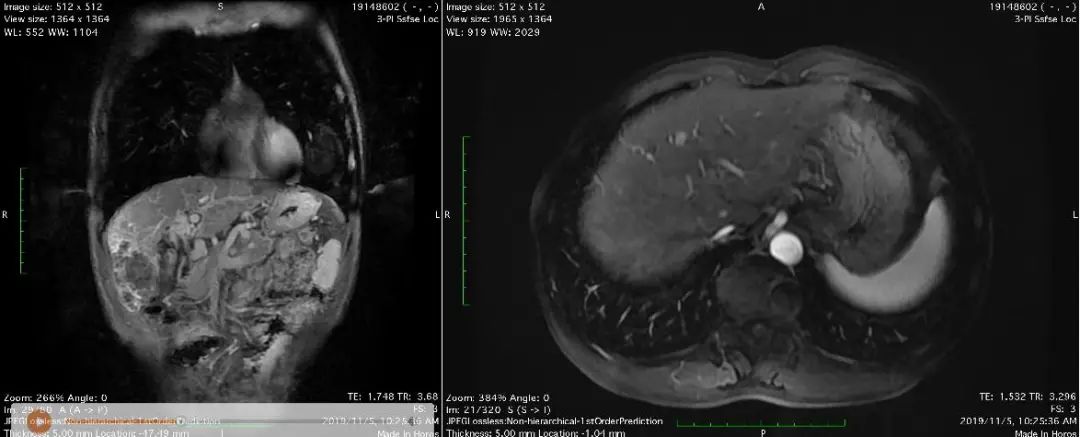

病例简介患者女性,46,因体检发现肝占位1周,于2019年2月就诊于浙江大学医学院附属第二医院。7年前因左乳腺肿物于外院行左乳腺癌改良根治术,术后未行放化疗。&n...